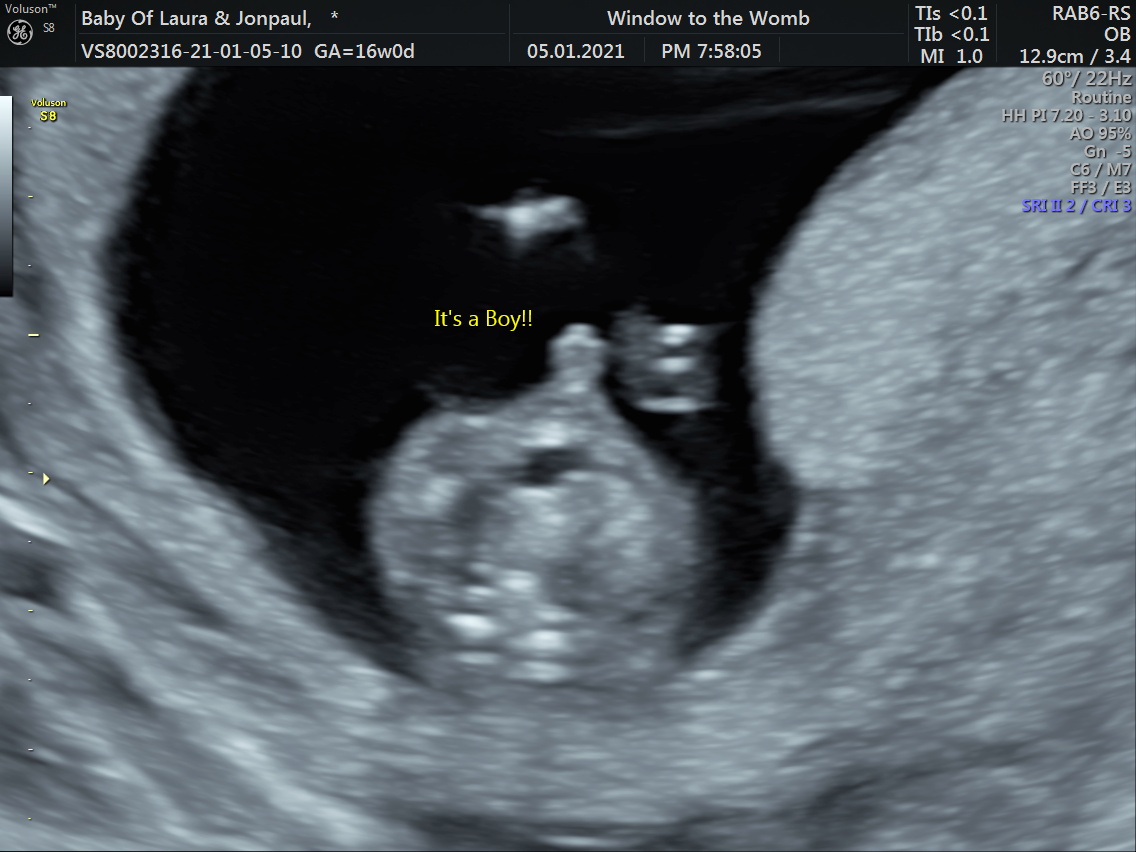

Scratch that I had a gender scan today just over 15 weeks it’s a boy I’m completely crushed. Didn’t think I would feel this bad. How long after having a baby can I sway?

How sure were they? Usually they don't give confirmation till 18+.

Attachment 43098Attachment 43099

These were from a video I got not sure if that is the penis at the end

Attachment 43110Attachment 43111Attachment 43112

Got the potty shots